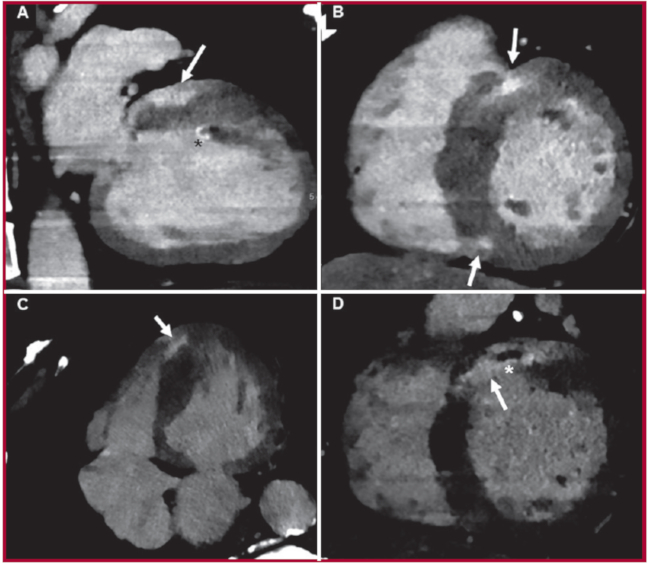

En las imágenes obtenidas 5 minutos luego de la administración de contraste, se evidenciaron múltiples áreas focales de realce tardío de patrón predominantemente intramiocárdico (Figura 2). Se destaca además, la identificación de núcleo hipodenso dentro del área de realce transmural anteroseptal basal (Figura 2D), compatible con obstrucción microvascular. También se observó mínimo realce subendocárdico en el nivel anterior, anterolateral medio y en nivel del músculo papilar anterolateral (Figura 2A), y del ápex del ventrículo derecho (Figura 2C). Utilizando mapas de iodo, se calculó un VEC de 36%.

El defecto de llenado en el nivel de la orejuela izquierda evidenciado durante la adquisición arterial (Figura 1C), resolvió completamente en la adquisición en tiempo tardío (Figura 2A), que confirmó la presencia de estasis sanguínea sin trombo en la orejuela.